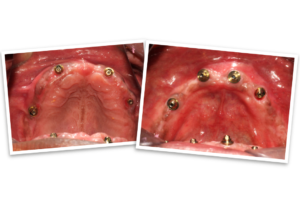

The day of the procedure arrived. Our team strategically placed four implants each in Mr. B’s upper and lower jaw (maxilla and mandible). The immediate denture was then securely fixed onto the implants, immediately providing him with a functional and aesthetically pleasing smile.

Three months later, we switched from the provisional denture to a permanent set of hybrid dentures, offering even greater comfort and durability. Mr. B now faces the world with renewed confidence.